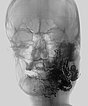

Laterale Ansicht einer digitalen Subtraktionsangiographie nach Injektion in die linke Arteria carotis externa. Die AVM ist als diffuser, netzartiger Nidus mit direktem, starken venösen Abstrom zentral in der linken Wange erkennbar (Fast-flow-Malformation).

Laterale Ansicht, DSA nach Anspritzen der linken Arteria carotis interna. Auch aus der Arteria carotis interna erfolgt eine massive Versorgung des Nidus der AVM, vor allem über die Arteria ophthalmica und den Truncus meningohypophysealis.

Dies erschwert die Embolisationstherapie erheblich.

DSA, anterior-posteriore Ansicht, nach Anspritzen der rechten A. carotis communis. Auch aus der kontralateralen rechten A. carotis externa und A. facialis rechts wird der Nidus der AVM an der linken Wange gespeist.